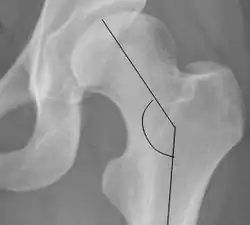

| Cervical diaphyseal angle |

The angle formed between the femoral neck and femoral diaphysis | 120° to 140°